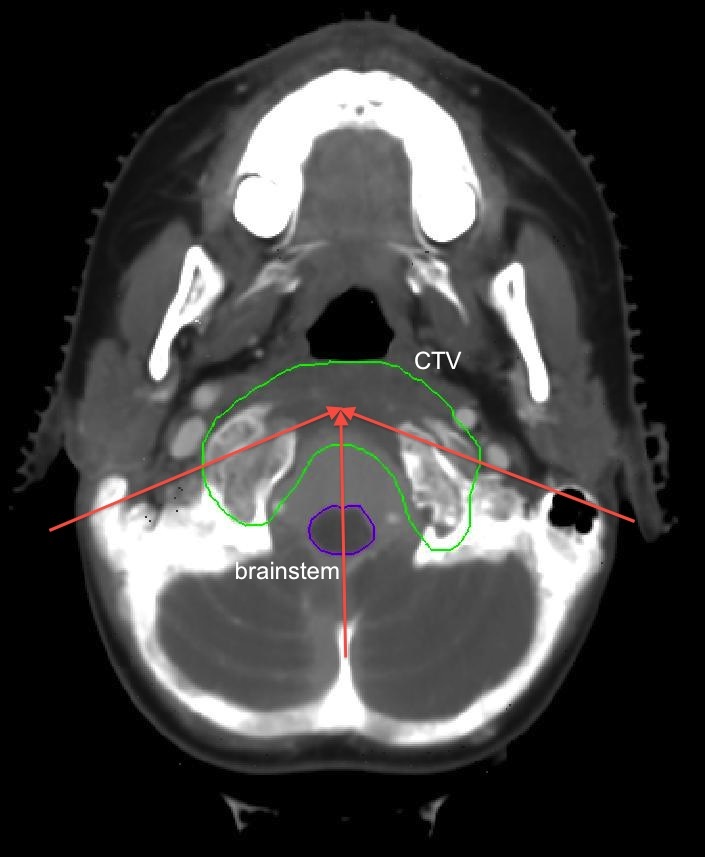

3.2 Chordoma

Three proton beams are used in the plan for this chordoma case. They are in the transverse plane at gantry angles of 110 degrees, 180 degrees and 250 degrees (see the CT image in Figure 3). The total number of beamlets is 9,623. The dose grid is 8810377 voxels. The voxel size of the dose grid is 2 mm 2 mm 2.5 mm. We assume 3 mm setup uncertainty and 5% range uncertainty. The raw dose-fluence matrices of the 29 scenarios used for this case total to 16.3 Gb in size. Each individual Pareto optimal plan optimization takes up to 5 minutes on a single 2.66G Intel Xeon CPU.